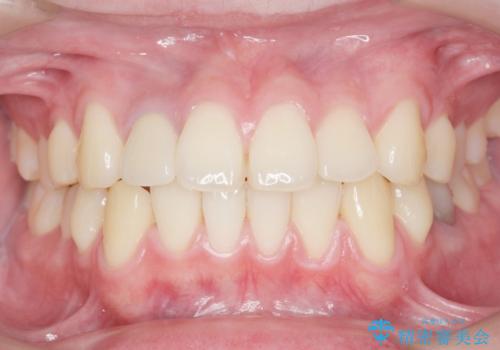

他院で入れたセラミッククラウンの色が気に入らない 20代男性

- 他院で入れたセラミッククラウンの色が気に入らないことを主訴に来院された患者様です。

高校生の時に部活で前歯をぶつけて神経が死んでしまい、歯が黒く変色したためセラミッククラウンで治療したとのことでした。

精査したところ、透過性のあるセラミッククラウンで治療されており、内側の黒い土台が透けてクラウンが黒ずんで見えていました。

土台を白いファイバーコアにやりかえたのち、土台の色を透過させないジルコニアフレームを用いたセラミッククラウンによる治療を行いました。

失活(神経が死んでしまっていること)により黒くなった歯根が透けて歯ぐきも黒ずんで見えるため、歯肉移植の手術も提案しましたが、そこまでは気にならないとご希望されませんでした。

自然な仕上がりにご満足頂けました。

治療終了時には「修正や仮付けをしてもらえて納得のいく治療を受けられました。この病院にして良かったです!」とおっしゃって下さいました。

クラウンの種類:オールセラミッククラウン スペシャル